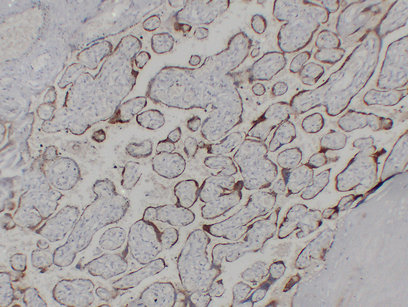

Immunohistochemistry analysis of paraffin-embedded Placenta using Choriogonadotropin Subunit beta 3/7 antibody.High-pressure and temperature Sodium Citrate pH 6.0 was used for antigen retrieval.

Glycoprotein hormones are heterodimers consisting of a common alpha subunit and an unique beta subunit which confers biological specificity. CG is produced by the trophoblastic cells of the placenta and stimulates the ovaries to synthesize the steroids that are essential for the maintenance of pregnancy. The beta subunit of CG is encoded by 6 genes which are arranged in tandem and inverted pairs on chromosome 19q13.3 and contiguous with the luteinizing hormone beta subunit gene.

推荐稀释比 IHC:1/100-1/500